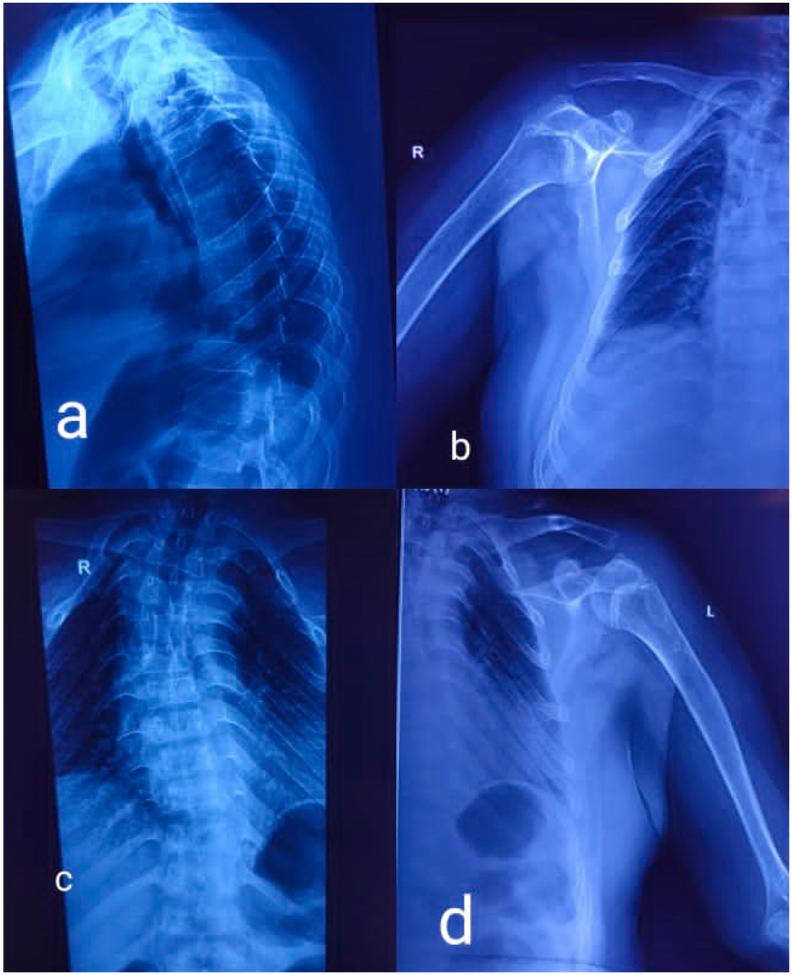

This case presents a unique incidental finding of skeletal dysplasia in a fifty-year-old male patient who presented with osteoarthritis. Eventual workup uncloaked the presence of cleidocranial dysplasia and spondyloepiphyseal dysplasia. The patient in this case had both dysplasias at the same time.

Cleidocranial dysplasia and Spondyloepiphyseal dysplasia are two uncommon autosomal dominant dysplasia's that are often diagnosed in early life and can have serious consequences, including death. It is critical to diagnose a child early in life. Radiology findings from a thorough skeletal examination aid in the early detection of numerous dysplasia's, which helps improving quality of life and allowing for effective treatment.

本病例展示了一名50岁男性骨关节炎患者骨骼发育异常这一独特的偶然发现。最终检查揭示了锁骨颅骨发育不全和脊椎骨骺发育不良的存在。该病例患者同时患有这两种发育异常。

锁骨颅骨发育不全和脊椎骨骺发育不良是两种罕见的常染色体显性发育异常,通常在生命早期被诊断出来,可能会产生严重后果,包括死亡。在儿童生命早期进行诊断至关重要。全面骨骼检查的影像学结果有助于早期发现多种发育异常,这有助于提高生活质量并实现有效治疗。